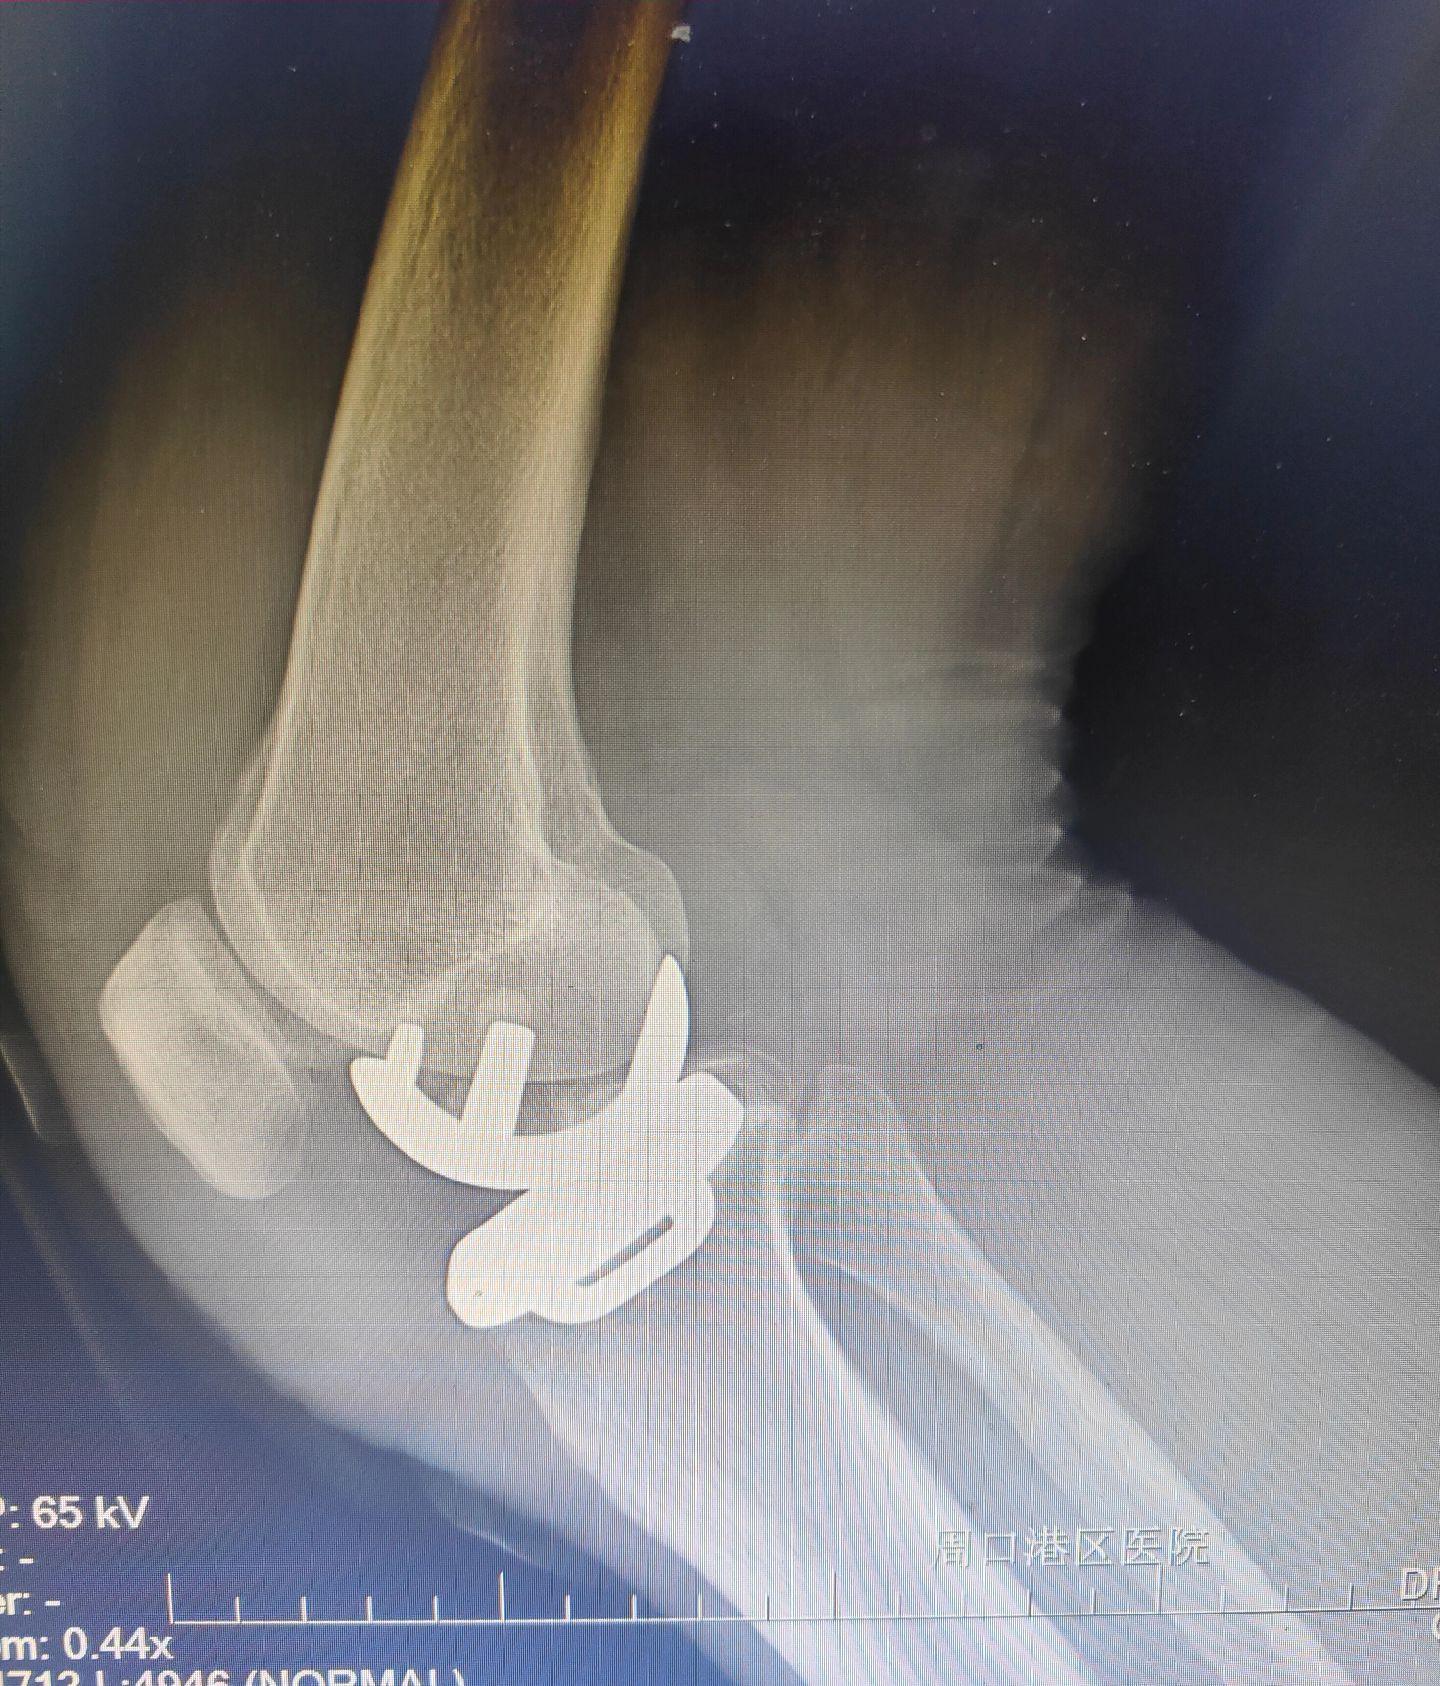

单髁置换术。(看图猜假体)每款假体都有自己的优点,不要单纯追求国产或进口,也不要单纯追求活动平台或固定平台,适合自己才是最好的。愿每一位病人都能快速顺利康复🌹